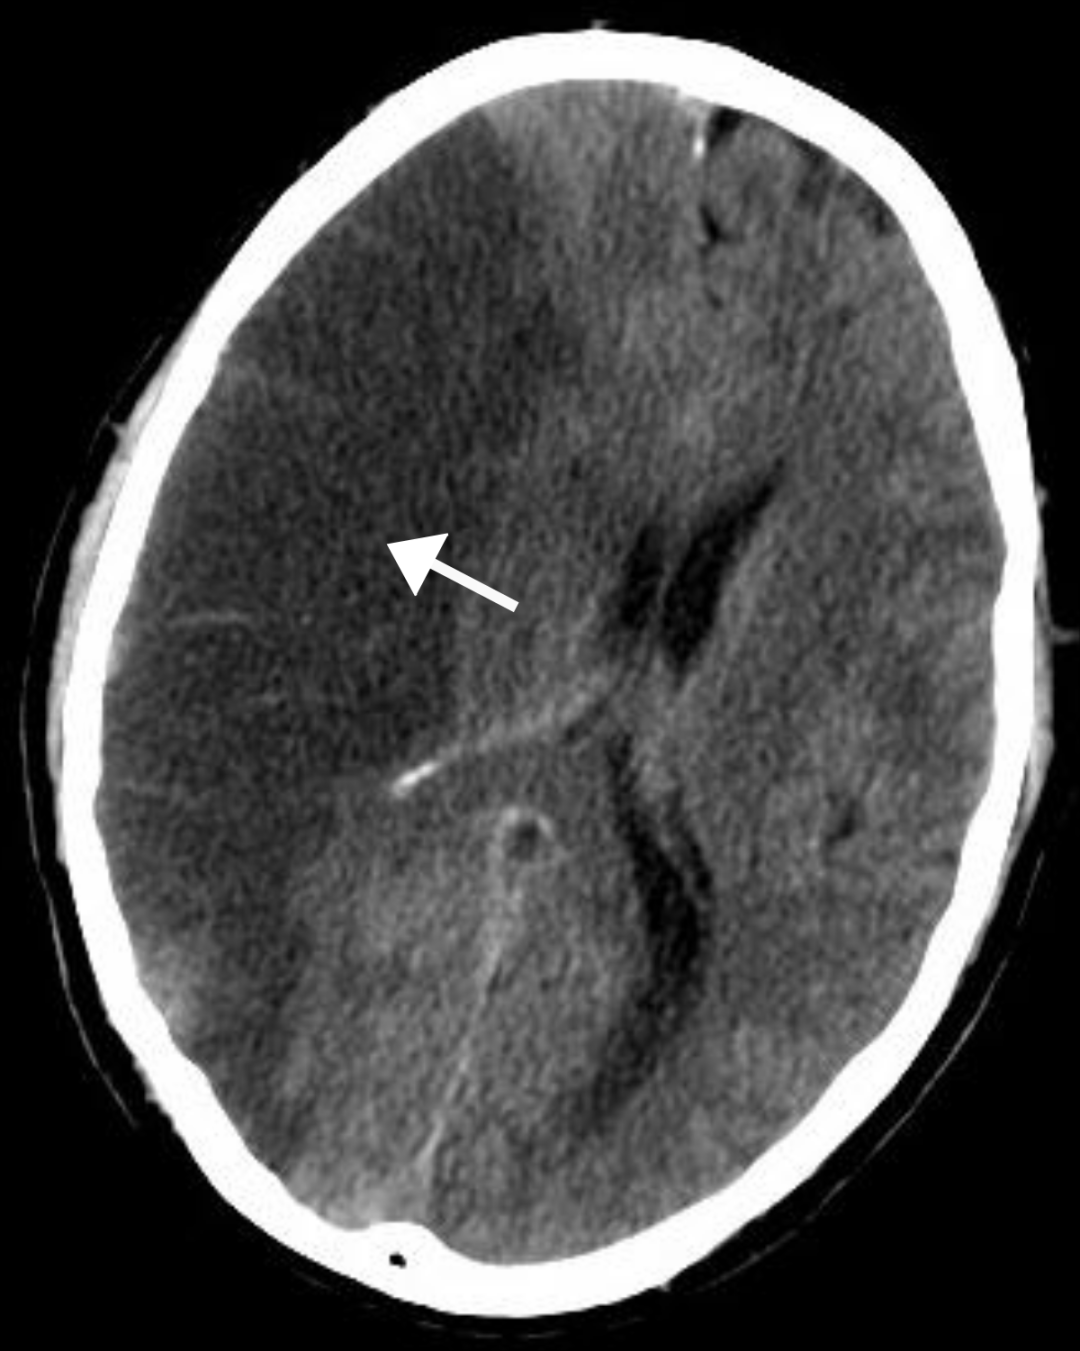

中风,一种因大脑血流不畅导致细胞死亡的疾病,一直以来都是国际社会的一个顽疾,给澳洲社会也造成了重大伤害。

中风对于大脑的影响是迅速的,每分钟有190万个脑细胞死亡。

许多患者在遭受永久性损伤后才接受治疗,导致痊愈后生活严重受到影响。

在面临中风患者每分钟百万数量的脑细胞死亡的恐怖情况下,研究人员相信他们的新药ARG-007可能会改变这一现状,有效帮助患者和医疗人员争取到宝贵的治疗时间。

研究人员说,其药物旨在通过鼓励特定细胞“冬眠”来防止脑细胞死亡。

脑细胞死亡是由缺氧引发的,并且在中风后“几乎立即”开始。

“这些钙流入脑细胞,这基本上会导致它们死亡并几乎崩溃。它只是引发了脑细胞死亡的循环……。”

“本质上,我们要做的就是让脑细胞冬眠并保护它们免于死亡,直到患者接受到去除血栓的治疗。”

12小时后,这些进入休眠的细胞重新开始正常工作。